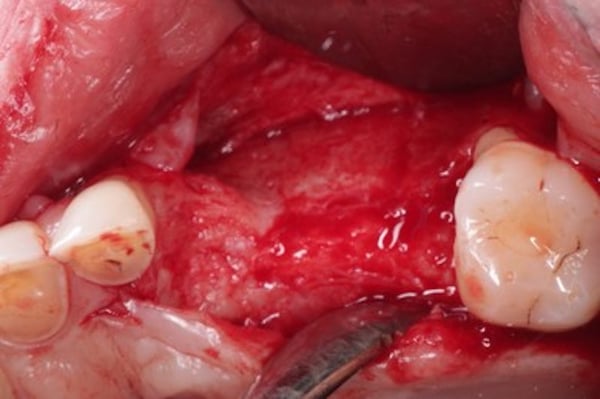

When performing extensive GBR, we want to insure the primary closure of the flap margins over the graft and membrane. In this example, following the placement of the DALI Bone graft and OsseoSeal membrane, the buccal flap was released from the periosteum for passive mobilization (Pictures 1,2,3,4). Prior to suturing the flap margins together at the crest, a periosteal-relief suture is placed in order to prevent any tension from pulling back the flaps (Picture 5). This allows the flaps to stay relaxed without needing to be pulled together. Afterwards, sutures are used to approximate the buccal and palatal flap margins to achieve primary closure that will endure throughout the initial healing period (Picture 6). We see that following 2 weeks of healing, proper primary closure allowed the grafted site to remain covered (Picture 7).